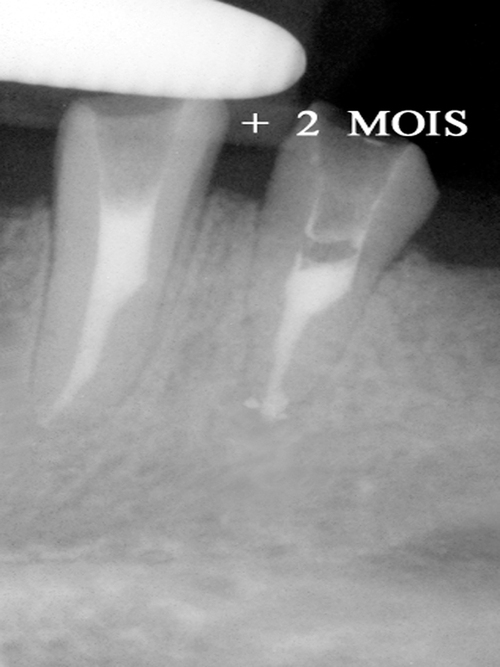

Cet acte simple donne de très bons résultats lorsque le canal peut être facilement désobturé. Les suites opératoires sont indolores et la cicatrisation osseuse est visible en quelques mois (fig.17).

fig. 17 – la guérison osseuse est obtenue en 2 mois